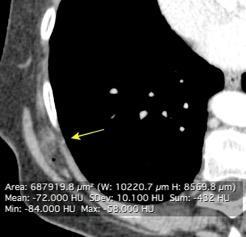

Densidad similar al músculo con estriaciones internas de grasa

Hallazgo incidental . Región infraescapular 2% de TC del tórax. Bilateral 60%.

Burt AM et al. Imaging review of lipomatous musculoskeletal lesions. SICOT J2017/ Murphey MD et al. From the archives of the AFIP: benign musculoskeletal lipomatous lesions. Radiographics. 2004